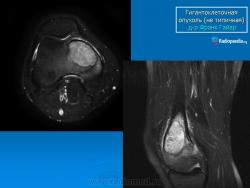

Гигантоклеточная опухоль.

Случай 6: (нетипичный)